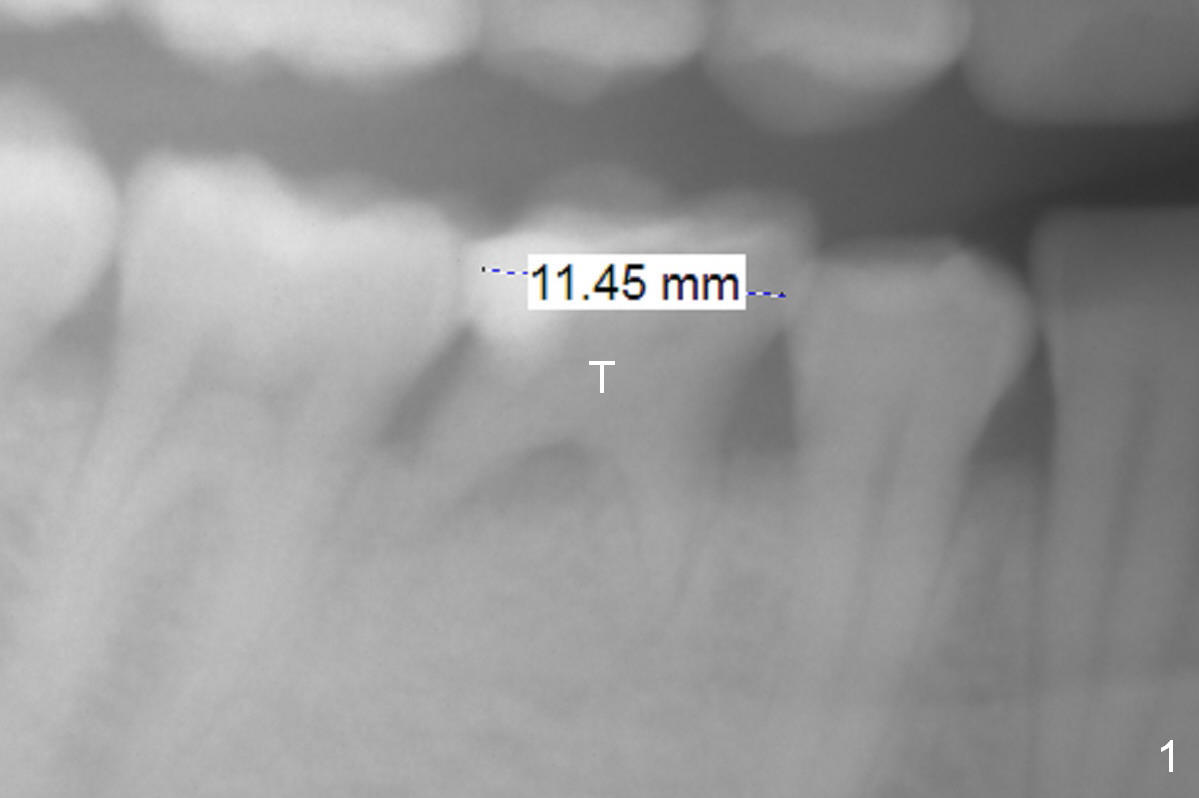

A 39-year-old woman has periodic mobility and pain of the lower right 2nd primary molar. It appears that the mesiodistal width of the tooth has decreased in the last 7 years (Fig.1,2). After extraction and Clindamycin/10 drops of 1:1000 Epinephrine gauze for 3 times, use LR plastic quadrant tray and PVS to take impression of the socket for education purpose. Try using Magic Expanders, but Magic Drills will be most likely used to finalize the osteotomy, since the bone density does not seem to be low. The initial depth will be 11 mm for IBS implant (Fig.3).